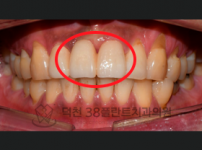

치료전후